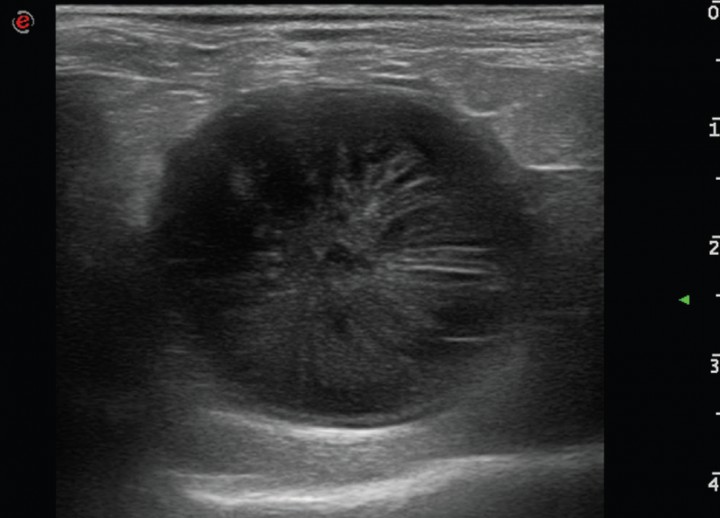

El examen ecográfico fue realizado con sondas semiconvex (3-9 MHz) o lineales (4-13 MHz) (Esaote, Mylab 70, Barcelona, España) según el tamaño del paciente; los animales se posicionaban en decúbito lateral, supino o en estación para confirmar que el contenido de la vesícula biliar era inmóvil. En el examen ecográfico se evaluó el modelo del contenido biliar, grosor de la pared (normal < 3 mm),[ Spaulding KA. Ultrasound corner: Gallbladder Wall thickness. Vet Radiol & Ultrasound 1993; 34:270-272. ] aspecto del tejido adyacente a la vesícula, ecogenicidad del hígado (normal, hiperecogénico, hipoecogénico, o heterogéneo), si existía efusión peritoneal y alteraciones ecográficas en otros órganos. El grado de distensión de la vesícula biliar se evaluó en corte longitudinal (valores de referencia: longitud 3–7,8 cm y profundidad 1,4–4,3 cm) y en corte transversal (valores de referencia: anchura 1,8–4,9 cm y profundidad 1,5–4,1 cm).[ Atalan G, Barr FJ, Holt PE: Estimation of the volumen of the gall bladder of 32 dogs from linear ultrasonographic measurements. Vet Rec, 2007;160: 118-122. [PubMed] ] El modelo del contenido de la vesícula biliar se dividió en 5 tipos (clasificación modificada de JG Besso[ Besso JG, Wrigley RH, Gliatto JM, Webster CRL: Ultrasonographic appearance and clinical fidings in 14 dogs with mucocele. Vet Radiol & Ultrasound, 2000; 41: 261-271. [PubMed] ] y J Choi[ Choi J, Kim A, Keh S, Oh J, Kim H, Yoon J. Comparison between ultrasonographic and clinical fidings in 43 dogs with gallbladder mucoceles. Vet Radiol & Ultrasound, 2014; 55:202-207. [PubMed] ]): Tipo I, sedimento ecogénico inmóvil (Fig. 1); Tipo II, patrón estriado (sedimento ecogénico inmóvil en el que se visualizan estriaciones hipoecogénicas finas y mal definidas desde el interior hacia la pared de la vesícula; Fig. 2); Tipo III, en forma de estrella (material ecogénico en el centro de la luz vesical que emite prolongaciones hipoecogénicas hacia la periferia presentando forma de estrella; Fig. 3); Tipo IV, combinación de patrón de kiwi-estrella (sedimento ecogénico ocupando la zona central de la vesícula biliar en donde se producen prolongaciones con finas estriaciones hacia la periferia; Fig. 4), Tipo V, modelo de kiwi (material ecogénico inmóvil con finas estriaciones hipoecogénicas atravesándolo y ocupando el centro de la luz vesical; Fig. 5).

<p>Imagen ecográfica de la vesícula biliar en corte transversal. Modelo de mucocele biliar de Tipo I: se observa la vesícula biliar distendida con gran cantidad de contenido ecogénico inmóvil en su interior.</p>

Figura 1

Imagen ecográfica de la vesícula biliar en corte transversal. Modelo de mucocele biliar de Tipo I: se observa la vesícula biliar distendida con gran cantidad de contenido ecogénico inmóvil en su interior.